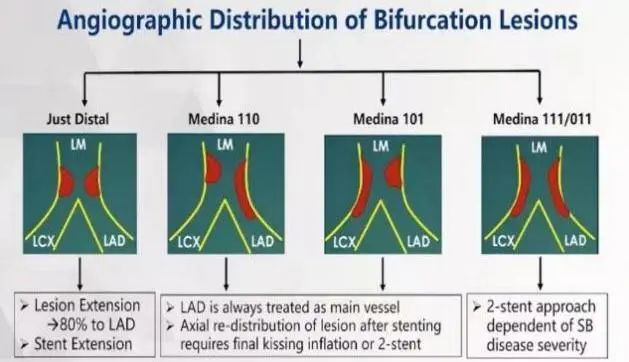

考虑为Medina(1,1,1)真分叉病变,且根据Definition定义为复杂分叉,拟采用双支架术式。